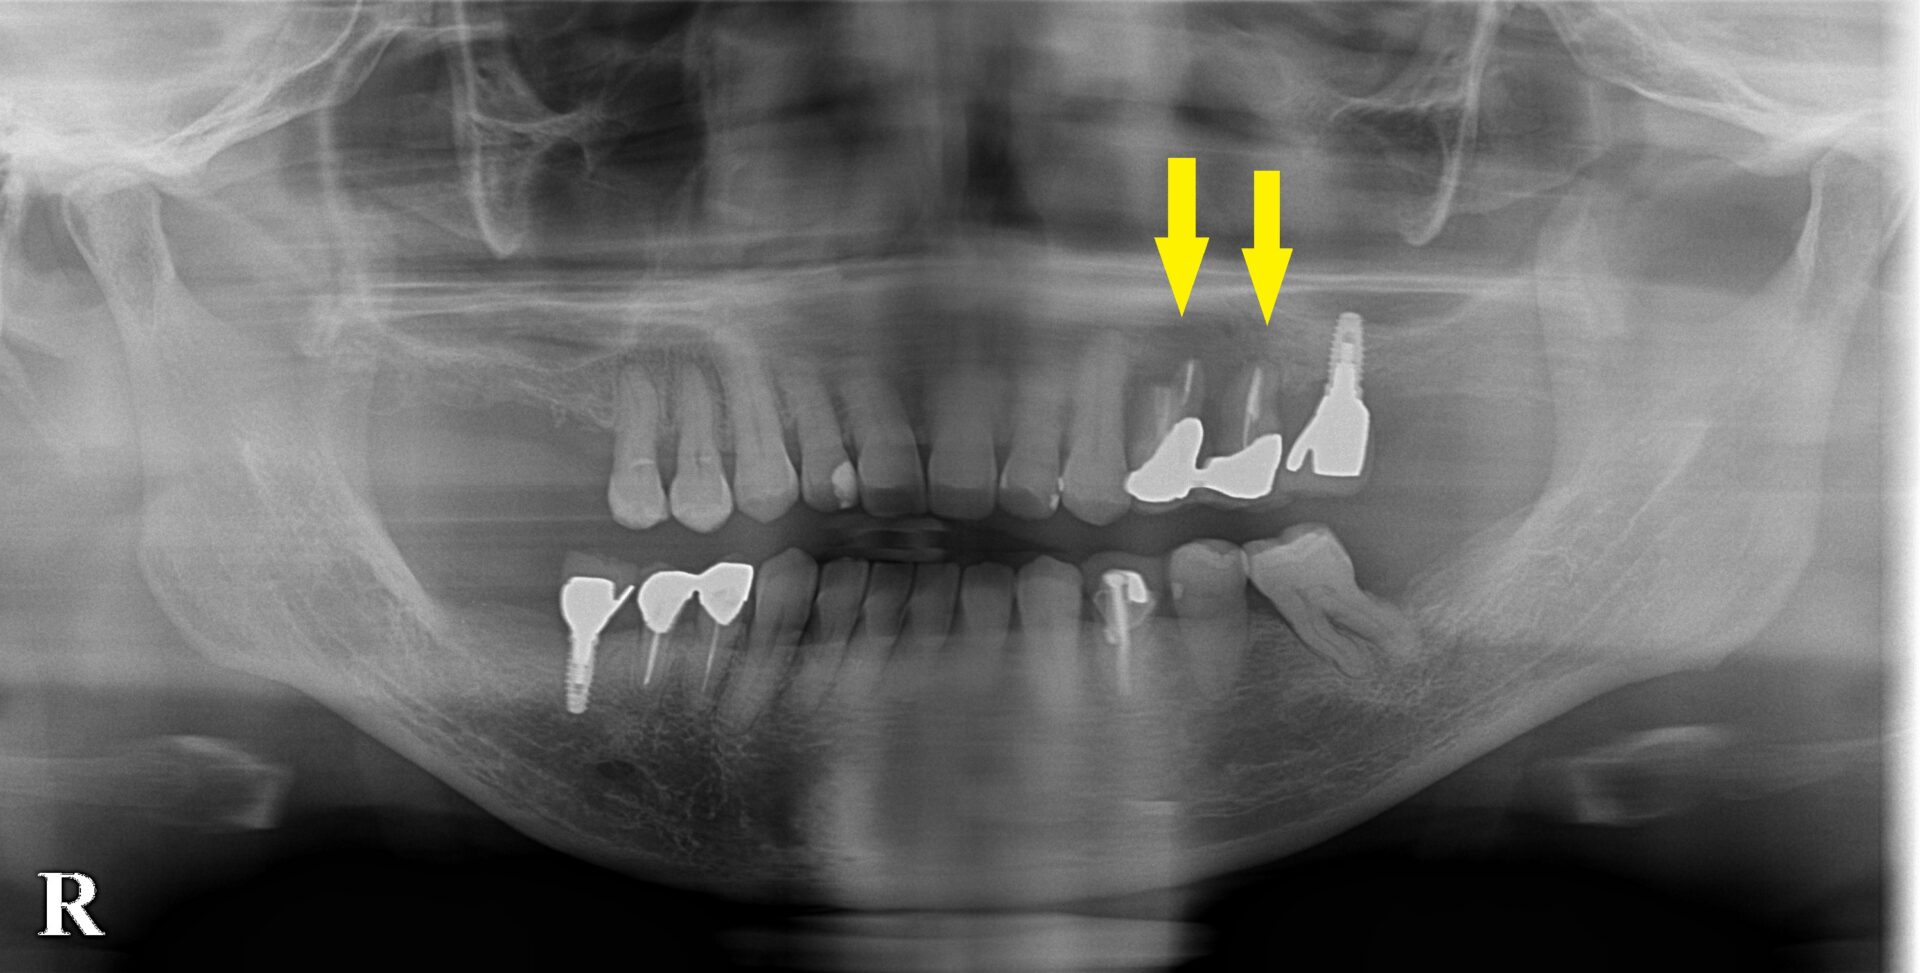

以前に2本のインプラント治療を、他院で受けられている患者様です。

今回は、左上顎の小臼歯2本が、被せものの中で崩壊状態となり、破折も起こしていて、抜歯しなければならない状態でした。

ただこの部位は骨が少ないので、インプラントは無理だろうと言われたそうです。

抜歯後3か月でCTを撮ってみたのですが、骨の幅も、高さも足りません(下の写真2段目)。